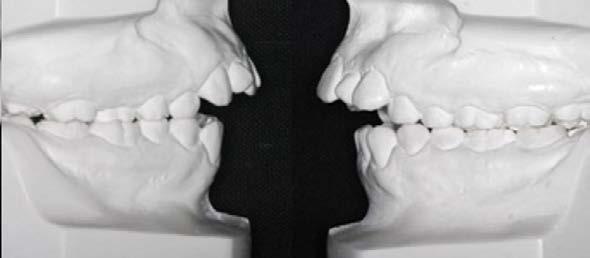

Objetivo: presentar un caso clínico de paciente con mordida abierta anterior, clase II y deglución atípica tratada con aparatología fija ortodóntica.

Caso clínico: paciente femenino de 19 años, patrón dolicofacial, perfil convexo, clase II esqueletal debido a una retrusión mandibular, mordida abierta anterior esqueletal, clase II molar, clase canina no establecida por mordida abierta, apiñamiento severo superior e inferior y deglución atípica.

Resultados: obtención de una clase canina I y clase molar II funcional, se corrigieron las sobremordidas horizontal y vertical, y se logró la coincidencia de líneas medias facial y dental. El manejo de la mordida abierta anterior se llevó a cabo por medio de la corrección del hábito de deglución atípica con la ayuda de spikes de resina, elásticos intermaxilares y arcos utility, y se obtuvieron buenos resultados estéticos, dentales y funcionales.